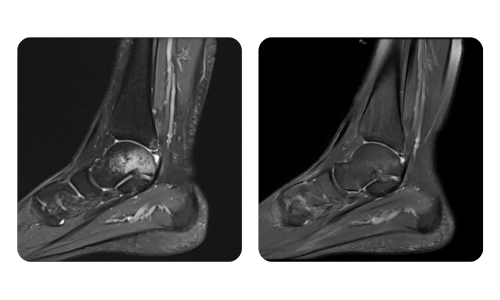

Der Fortschritt unserer Patienten, gemessen vor und nach der hyperbaren Therapie, spiegelt die Effizienz und die positive Wirkung der Behandlung wider. Entdecken Sie dokumentierte Ergebnisse der hyperbaren Therapie in der Klinik Hyperbarium Oradea, basierend auf klinischen Bewertungen und objektiven Daten, die signifikante Verbesserungen bei verschiedenen Erkrankungen belegen.